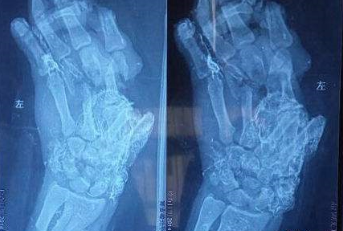

粉碎性骨折是非常严重骨折,作为完全性骨折,粉碎性骨折通常系指骨质碎裂成三块以上。由于粉碎性骨折的是病情非常中的骨折,所以通常需要进行手术治疗,而且还往往借助钢板、支架等进行固定,其目的主要是促进受伤部位骨头的恢复和生长。与其他骨折相比,粉碎性骨折手术难度更大,而且手术后效果愈合欠佳。

粉碎性骨折手术恢复受多种因素的影响,除骨折的严重程度外,手术方法是否得当的影响因素外,手术后的日常护理保健工作,特备饮食及后期局部康复训练对骨折的恢复都具有重要的意义和作用。由于骨折的恢复通常需要很长的时间,特别是粉碎性骨折更好的恢复的时间往往会更长。

对于粉碎性骨折,如果想借助治疗方式、康复锻炼、饮食等方面彻底恢复到骨折之前的状态及活动性,几乎是不肯能的。而粉碎性骨折系统治疗的其目的也是最大限度的恢复到骨折前的状态,尽可能避免或造成功能受限,影响的行走或者影响到身心健康等方面。

专家指出,粉碎性骨折虽然是非常严重的骨折,但及时规范治疗往往能很大程度上解决其基本功能问题,但也必须要面对和承认,粉碎性是最严重的骨折类型,其也往往面临愈合不不佳的情形。